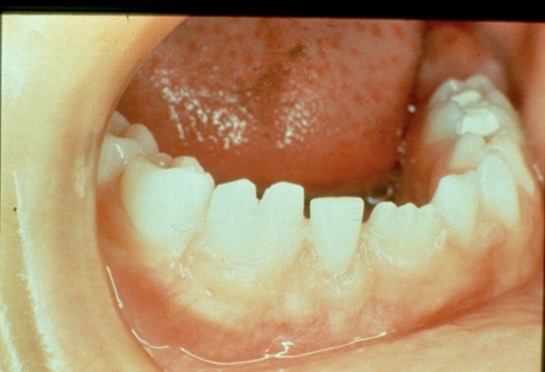

This child's teeth erupted like this. What is the condition?

Hutchinson's incisors from congenital syphilis